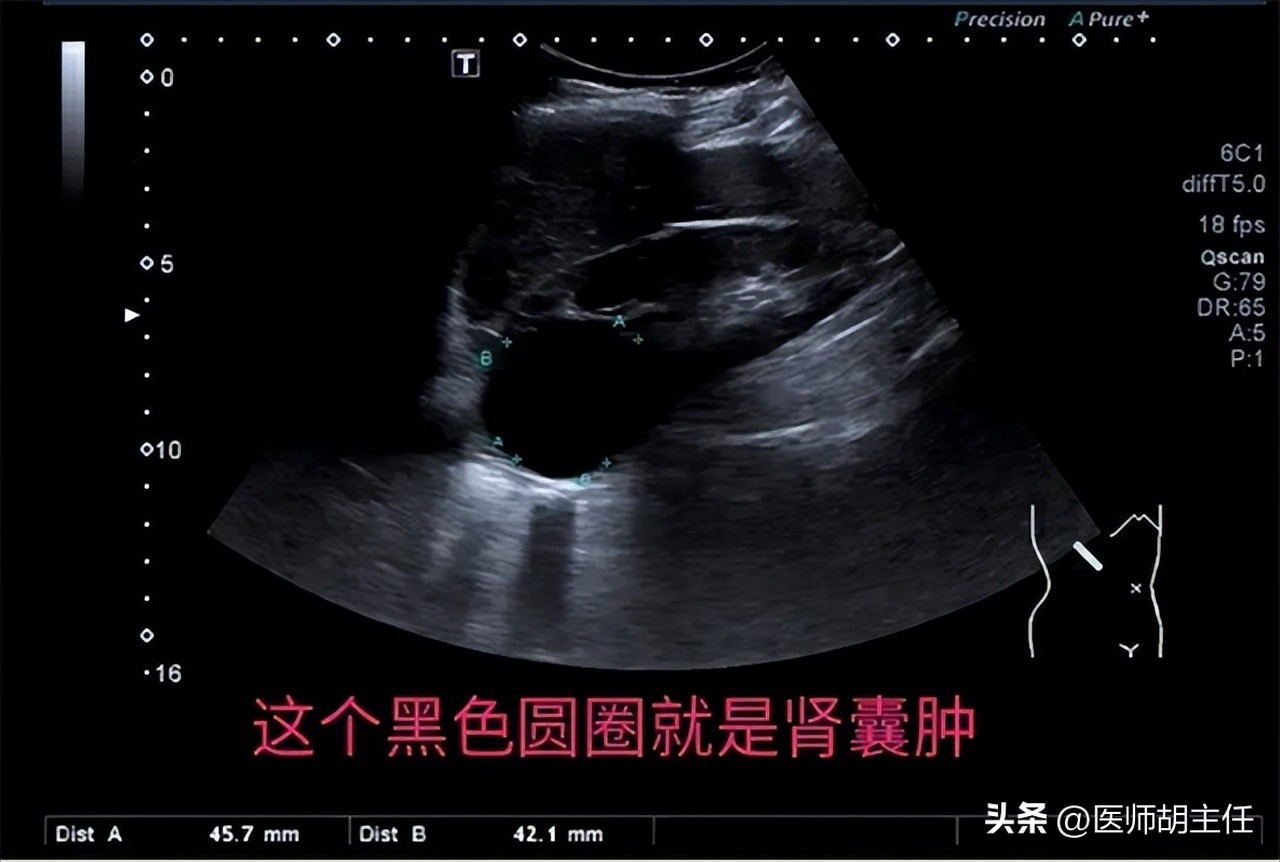

到了医院,医生给王先生做了肝脏B超,结果显示他的 肾囊肿大小为2厘米,囊肿边界清晰,呈规则的椭圆形,且血液结果并无异常 。

肾囊肿是成年人肾脏最常见的一种结构异常。

随着B超技术和CT技术的普遍应用,诊断为肾囊肿的人越来越多。50岁以上的人群,有大约三分之一被发现体内有大小不一样的肾囊肿。

研究发现,肾囊肿的发展速度很慢, 大部分囊肿的平均直径都在5毫米到10毫米左右,对肾脏和周围组织没有影响,一般不会有临床症状出现,只需要在6个月或者一年按时做B超检查,观察肾囊肿是否增大。

只有在肾囊肿的直径大于等于5厘米,或者有相关症状,比如腹痛、排便不畅等症状时,说明囊肿已经压迫到周围组织,则需要就医,对症治疗。